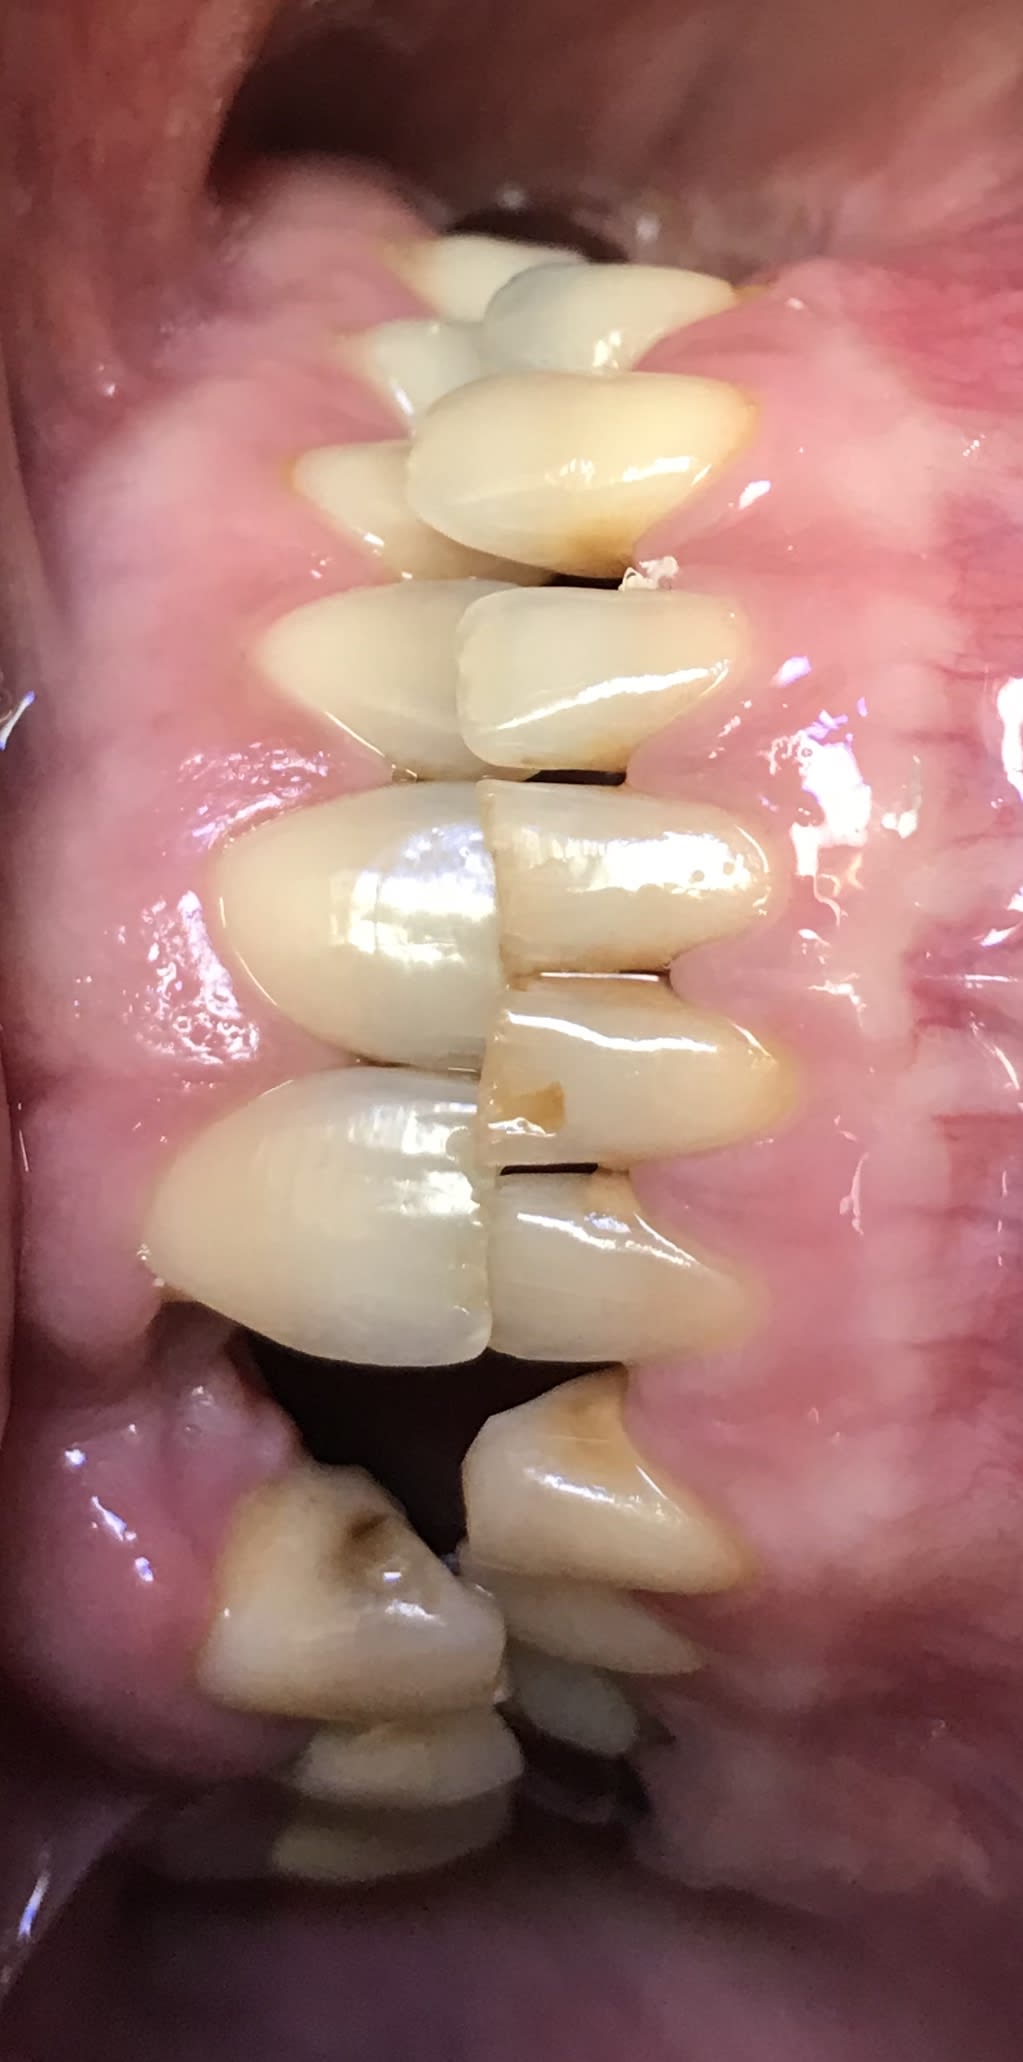

Tu me conseilles quoi pour ce cas ?

884954e6 01d1 48c7 b863 4d4bcc77abfc yfolk7 - Eugenol

D3638175 e2ed 4f34 9915 83de7130c18a o9ctwb - Eugenol

622cfde7 0b16 431d 8c0d 49a3406744f1 ivjo6s - Eugenol

7f6cbbb1 a54f 4995 b0d9 c69e9b952dd4 q6ipda - Eugenol

Pas de mylolyses , parodonte en acier trempé , cerveau calme , ça fonctionne apparemment .

Tu remplaces ce qui manque , tranquille .

Apres en haut , il ne doit pas y avoir beaucoup d os en vest ( 12 ) .

Alors là c est embetant si tune fais pas 1 implant mais un bridge ou autre , il faut enregistrer les trajets de fermeture , et tous les mvts , sur la table incisive et se les mettre de coté avant de toucher quoi que ce soit .